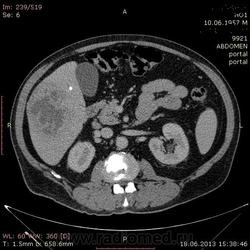

- https://radiomed.ru/sites/default/files/styles/case_slider_image/public/user/17529/img-0007-00001_3.jpg?itok=TEBWqlDr

На абсцесс похоже

На мой взгляд, абсцесс.

Тоже за абсцесс.

Cпасибо , коллеги.Сегодня больного прооперировали диагноз абсцесс правой доли печени.Оказывается больной когда - то получил тупую травму живота, об этом нам не говорил.....